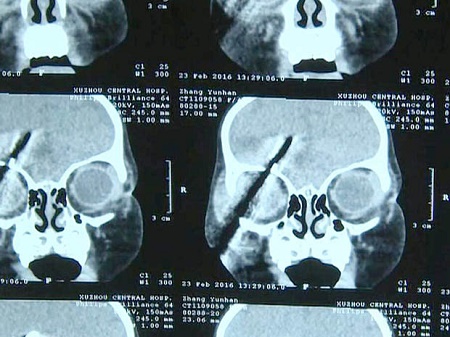

Doctors were faced with a highly sensitive operation to remove a screwdriver from the head of a toddler who was found with the tool embedded in her brain but successfully scaled it.

According to reports, the little girl identified as Han Han from Xuzhou City, in China’s eastern Jiangsu Province, was walking around the house unattended and managed to get her hands on one of the tools lying around. However, she was rushed to the hospital after she tripped and the screwdriver rammed some 10 centimetres (3.9 inches) into her right cheek.

Doctor Jiang said: "Seven centimetres (2.75 inches) of the screwdriver were inside the child’s skull, and 3 centimetres (1.2 inches) had penetrated her brain.

But luckily it missed her right eye and major blood vessels.

The tool was removed from Han Han’s skull after a meticulous surgery lasting some five hours, with reports saying she suffered very little blood loss in the process.